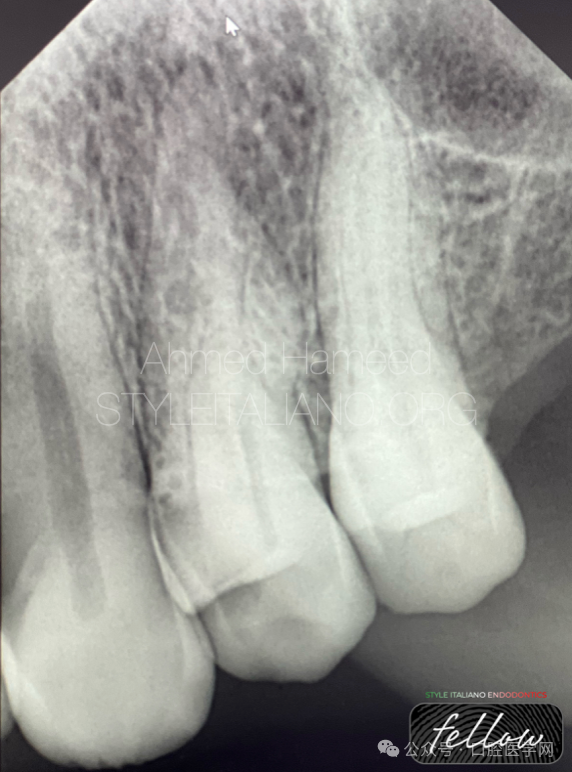

图6

在X光片上,一个可能指示根部存在广泛折断或裂纹的标志性特征是“J形病变”,它从牙根的根尖部延伸至冠部,且常伴有牙根吸收现象,这一点在此张X光片上非常明显。